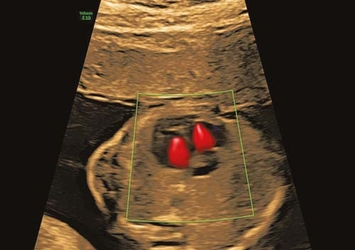

Detaillierte Herzuntersuchung

fetale Echokardiographie, optimal zwischen 20.–22. Woche

Farbdoppler-Ultraschall

Durchblutung bei Mutter & Kind